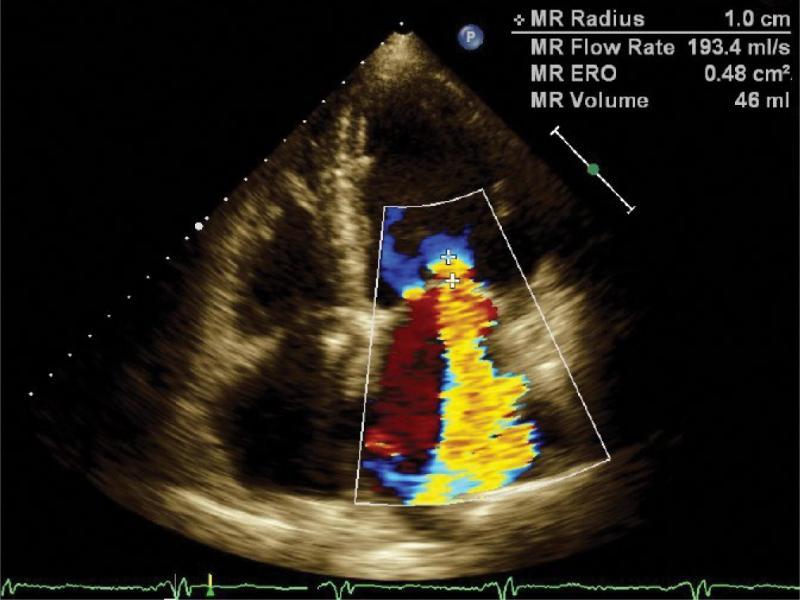

Normal mitral valve is rarely totally competent and a small amount of physiological regurgitation is often described. Pathological mitral regurgitation may be caused by degenerative changes in the form of leaflet fibrosis and calcifications, stiffening of their edges, leading to diastolic restriction (Carpentier type IIIA); mitral annular dilation (type I); mitral leaflet prolapse (type II) due to myxomatous changes or subvalvular apparatus damage; as well as systolic restriction (Type IIIB) due to left ventricular dysfunction. In addition to two-dimensional morphological assessment of the valve, echocardiography enables imaging and staging of valvular heart disease using color and spectral Doppler, and the PISA method (Fig. 5, Tab. 1).

A two-dimensional view of mitral regurgitation jet in color Doppler imaging in apical 4-chamber view. Altered color scale (Nyquist limit) and the PISA phenomenon along with the measurement of its radius (MS radius) and calculations of mitral effective regurgitant orifice area (MR ERO) and mitral regurgitant volume (MR volume)